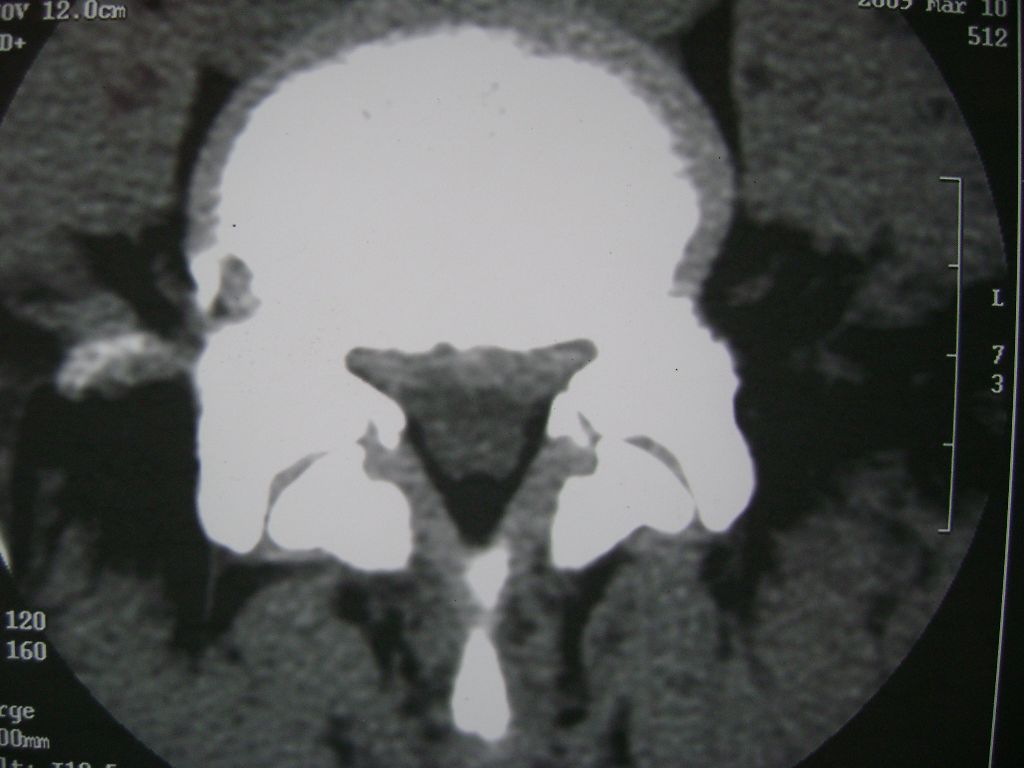

m  50  腰痛

两个椎盘均有膨出及突出改变,下一个尚有椎盘积气,后纵韧带钙化,另椎管脂肪过多症

椎间盘膨出,后纵韧带钙化,骨质增生

两个椎间盘中央型重度突出,黄韧带增厚。

两个椎间盘膨出并突出,下一个椎间盘变性;双侧黄韧带钙化。